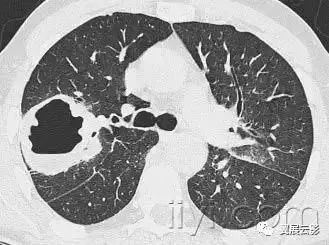

十九、肺实变:

平片和CT:肺实变表现为肺实质密度的均匀一致性增高,导致肺血管和气道壁边缘不清。有时可见含气支气管征。只有在极少数的情况下,肺实变的密度变化有助于鉴别诊断,例如脂性肺炎是密度减低,胺碘酮中毒时密度增高。

图示为多灶性的肺实变。